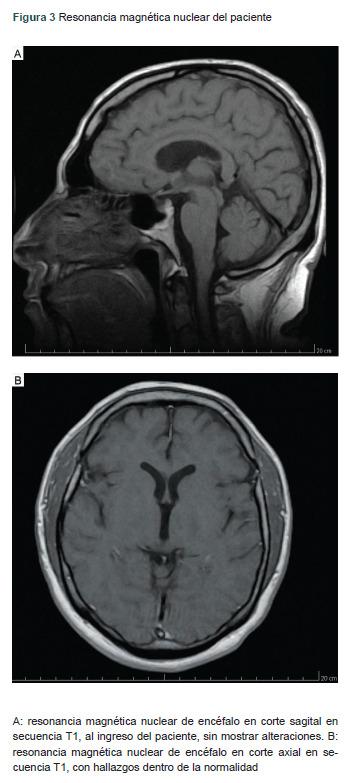

48-year-old man, with history of Pfizer-BioNTech vaccination against COVID-19, 5 days prior to the symptoms, who assisted to the Emergency room with blurred vision and diplopia; adding dysarthria, facial diplegia and left upper limb weakness after 48 hours. In his first evaluation it was found ophthalmoplegia, facial diplegia, decreased gag reflex, weakness of thoracic limbs, bilateral trapezius muscle and areflexia. Serum studies and nuclear magnetic resonance of the brain were performed without alterations. It was complemented with IgG anti-ganglioside GQ1b antibodies with a positive result. Once the diagnosis was confirmed, treatment was started with immunoglobulin calculated at 2 g per kg for 5 days. The patient was discharged once the immunoglobulin was administered with evaluation at 2 months without ataxia, ophthalmoplegia, areflexia and weakness.